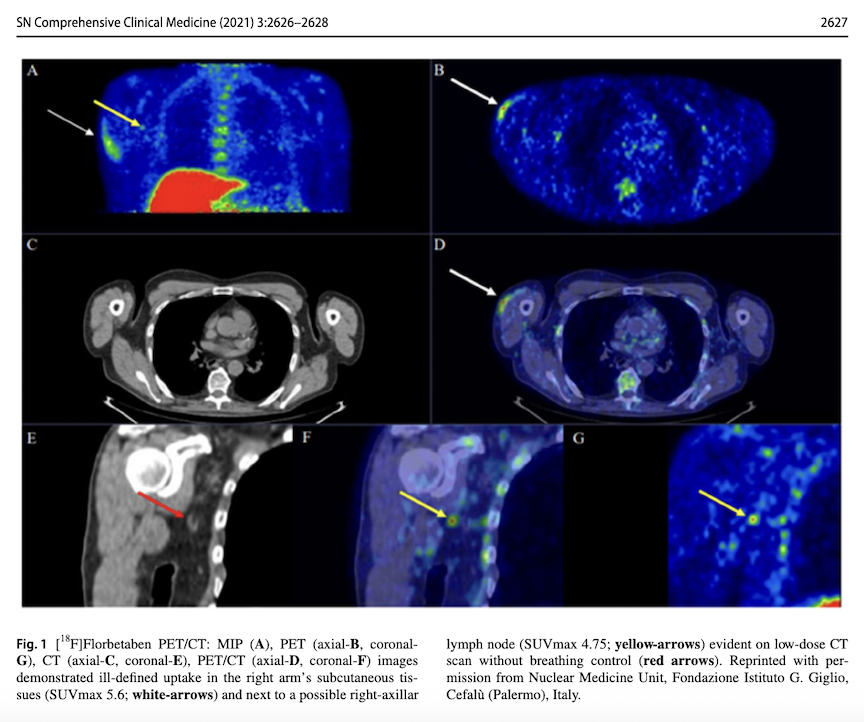

Dr McCairn cites the December 2021 scientific paper, "Subcutaneous Uptake on [18F]Florbetaben PET/CT: a Case Report of Possible Amyloid-Beta Immune-Reactivity After COVID-19 Vaccination" by Riccardo Laudicella et al., which he says should have set off alarm bells and stopped the vaccine roll-out, right then and there but he says many tenured and well-paid professionals knew better said nothing.

IMAGE 2: "Subcutaneous Uptake on [18F]Florbetaben PET/CT: a Case Report of Possible Amyloid-Beta Immune-Reactivity After COVID-19 Vaccination"

The in vivo study above involved the PET scan of a recently-vaccinated 70-year-old man, who was being tested for Alzheimer's disease. As part of the scan, he was administered Florbetaben, a diagnostic radiotracer, which lights up when it binds with β-amyloid plaques. This man's COVID injection site lit up, indicating that there was β-amyloid in the vaccine.